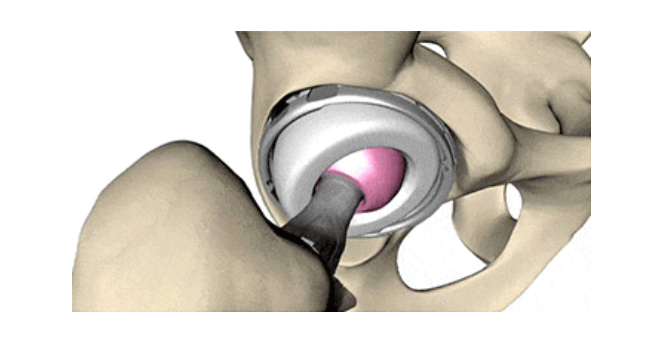

02人工髋关节置换术是什么

人工髋关节是用人造的髋臼和股骨头替代原来的“碗和球”。人工髋关节置换术是20世纪外科领域重要的技术创新,被称为“世纪性的手术”。全髋关节置换,需要处理髋臼一侧,功能优于股骨头置换,翻修率低,适合像郭大叔这样身体条件好、活动量较大的患者。